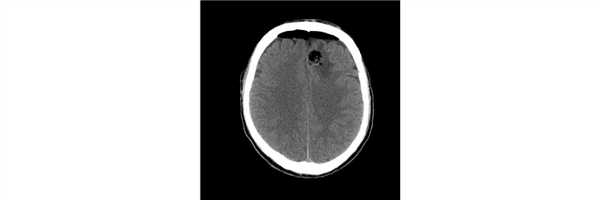

Пациент 20 лет дважды перенес эпилептический приступ - за 2 из 6 месяцев до консультации. По рекомендации невролога после второго приступа выполнил МРТ головного мозга, при которой выявлена внутримозговая опухоль левой лобной доли.

Проведена операция - радикальное удаление опухоли. Гистологический диагноз - плеоморфная ксантоастроцитома. Контрольная СКТ головного мозга не выявила остатков опухоли/послеоперационных осложнений.

Пациент выписан на 5 сутки после операции без неврологического дефицита.